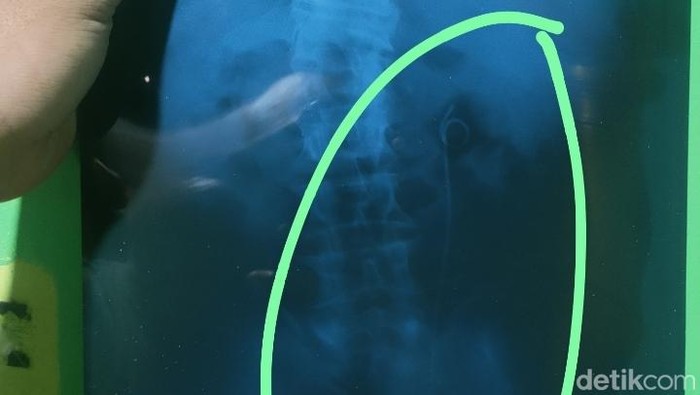

"Kalau terkait dengan selang yang tertinggal dalam bahasanya, itu adalah satu rangkaian prosedur dari operasi pengambilan batu saluran kencing. Jadi selang itu dipakai untuk mempertahankan saluran antara ginjal sama kandung kemih," kata Any, saat ditemui awak media di RSUD Kalisari Batang, dilansir detikJateng, Selasa (30/09).

"Itu kan salurannya kecil, kalau habis operasi itu kan mesti ada sisa-sisa darah, sisa-sisa butiran-butiran pasir mungkin yang dari batunya. Nah itu dimaksudkan untuk memperlancar aliran sisa-sisa itu dari ginjal ke kandung kemih. Karena kalau tidak ada selang itu tambah justru sakit," imbuhnya.

Dengan selang tersebut, menurut Any, saluran itu tetap terbuka dan melancarkan sisa operasi atau sisa kristal dari baru di saluran ginjal.

"Untuk melancarkan sisa-sisa operasi atau sisa-sisa kristal-kristal yang ada dari batu di saluran ginjal sampai ke kandung kemih, itu (selang) dipasang," tambahnya.